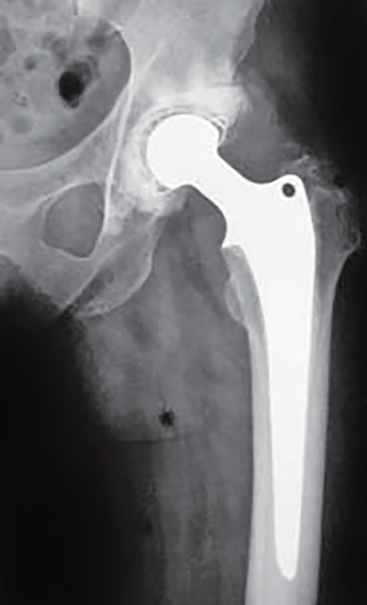

No prije svega treba istaći njegov pionirski teorijski i praktični rad na području mehanike živih sustava. Vrlo rano se povezao s liječnicima zagrebačkog Sveučilišta i započeo primjenjivati mehaniku na živim sustavima. Novim pristupom izučavanju takvih sustava dao je, primjenjujući inžinjerske metode, posebno mehanike, originalni i značajan doprinos ortopediji, anatomiji, fiziologiji i ergonomiji. Pritom je razvio usku suradnju s liječnicima, proširujući vlastito znanje temeljima medicine. Timski rad na području biomehanike dao je projekt prve domaće totalne endoproteze zgloba kuka, koja se proizvodila u Švicarskoj u tvornici “Sulzer”.